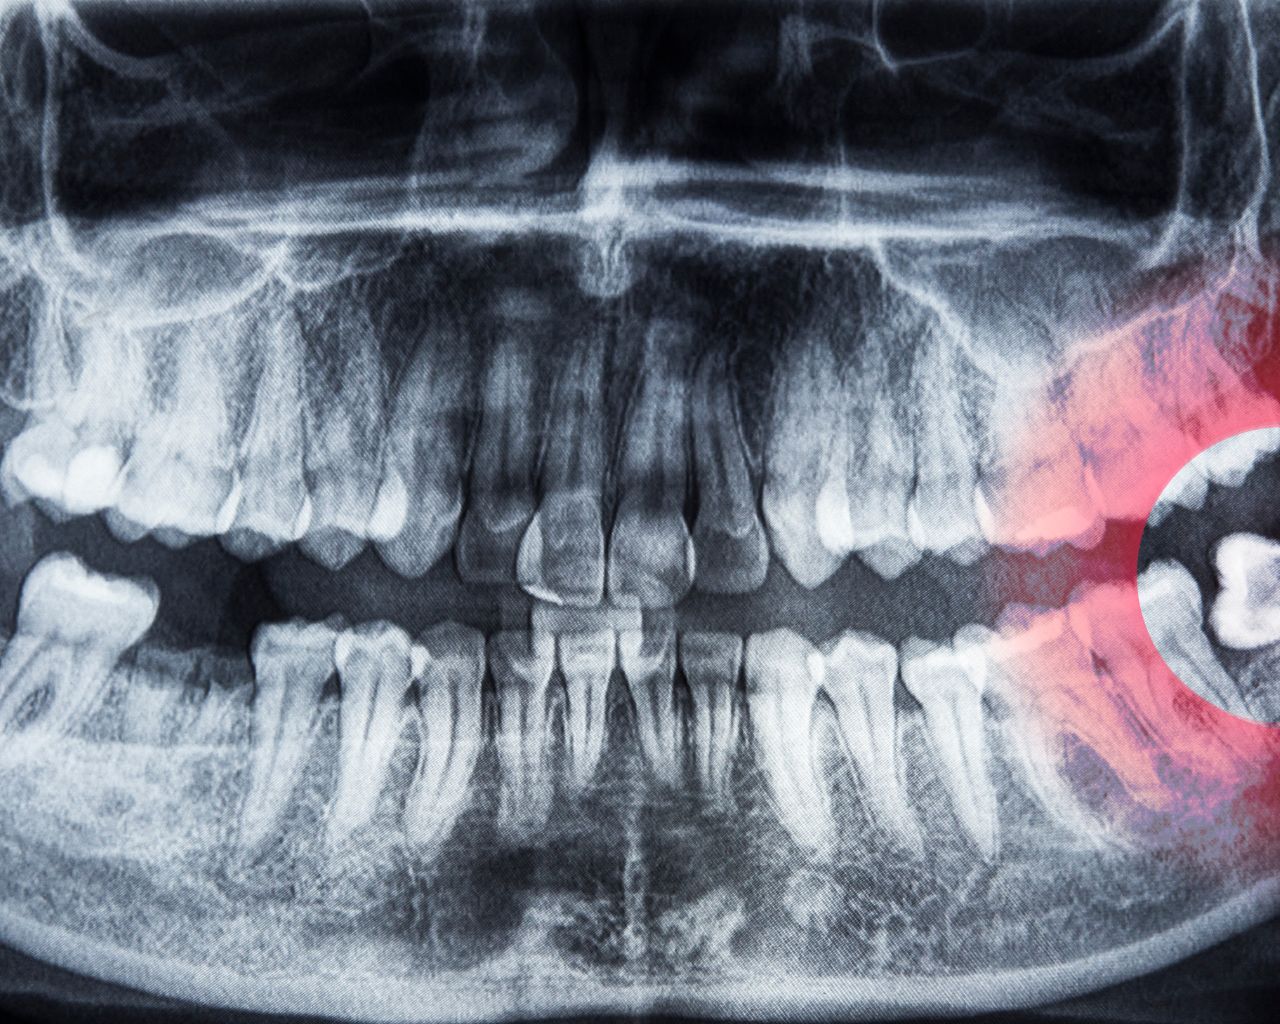

Infecciones y Abscesos

Las infecciones dentales y los abscesos pueden causar dolor intenso, hinchazón y fiebre. Es vital recibir tratamiento rápido para evitar que la infección se propague a otras partes del cuerpo.